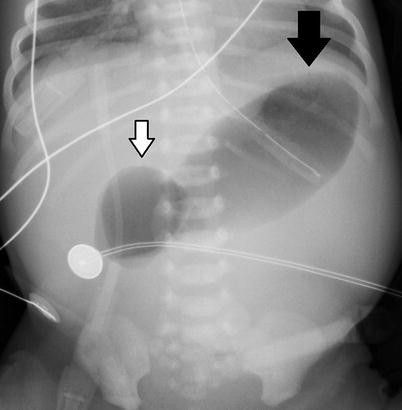

"Double Bubble" Sign in a patient with Duodenal Atresia

Duodenal Atresia

Congenital Anomaly